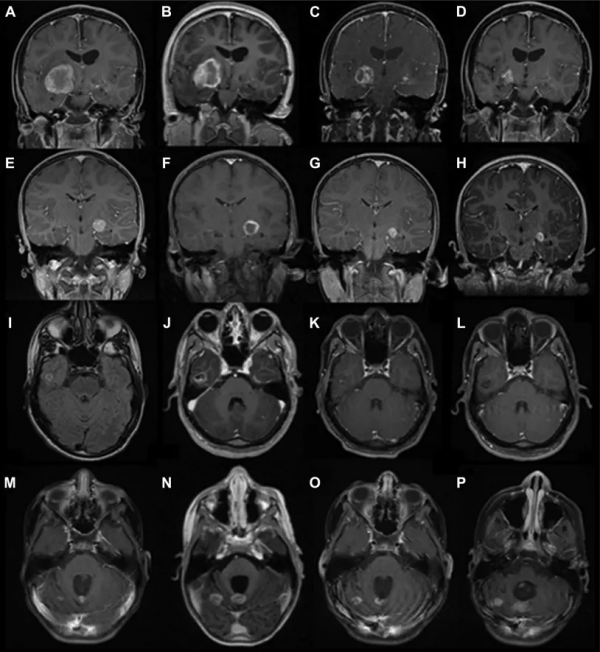

鐳射間質熱療LITT治療前後對比:所有層面都是軸位T1增強後圖像,除了圖I,軸位FLAIR序列腫瘤在消融前沒有增強。

· 神經節膠質瘤患者預消融(A),在她第一次LITT治療 (B),第一次LITT治療後6 個月和第二次LITT治療後3個月 (C),第一次LITT治療後 25 個月和第二次LITT治療後 22 個月 (D)。

· 腦膜瘤患者預消融 (E),LITT治療(F)、LITT治療後 4 個月 (G) 和LITT治療後 10 個月(H)。

· 低級別膠質瘤預消融軸向 FLAIR 影象(I),LITT治療後軸向 T1 增強後圖像 (J),LITT治療後4 個月 (K),和LITT治療後 21 個月 (L)。

· 軸位髓母細胞瘤患者LITT治療前 (M)、LITT治療 (N)、LITT治療後 1 個月 (O) 和 4LITT治療後數月 (P) 顯示進展。